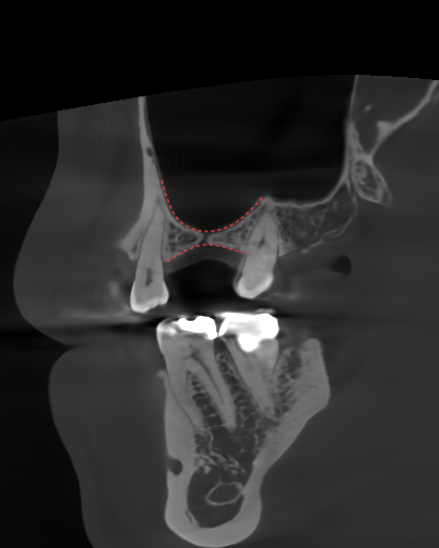

2. 치아 결손

민락 치과 에서 설명해 드린

충치가 진행된 어금니 외에도

눈에 띄는 부위가 있습니다.

그 앞쪽으로 결손된 곳으로,

텅 비어 있는 모습이 확인됩니다.

인접한 잇몸 조직에 비해서

다소 움푹 패인 모습을 보여주는데

이것은 치아가 결손된 부위가

그대로 방치된 케이스들에서

공통적으로 나타나는 문제입니다.

그건 바로 ‘골흡수’로

잇몸 조직이 자극을 받지 못하면

서서히 얇고 낮은 상태로 변합니다.